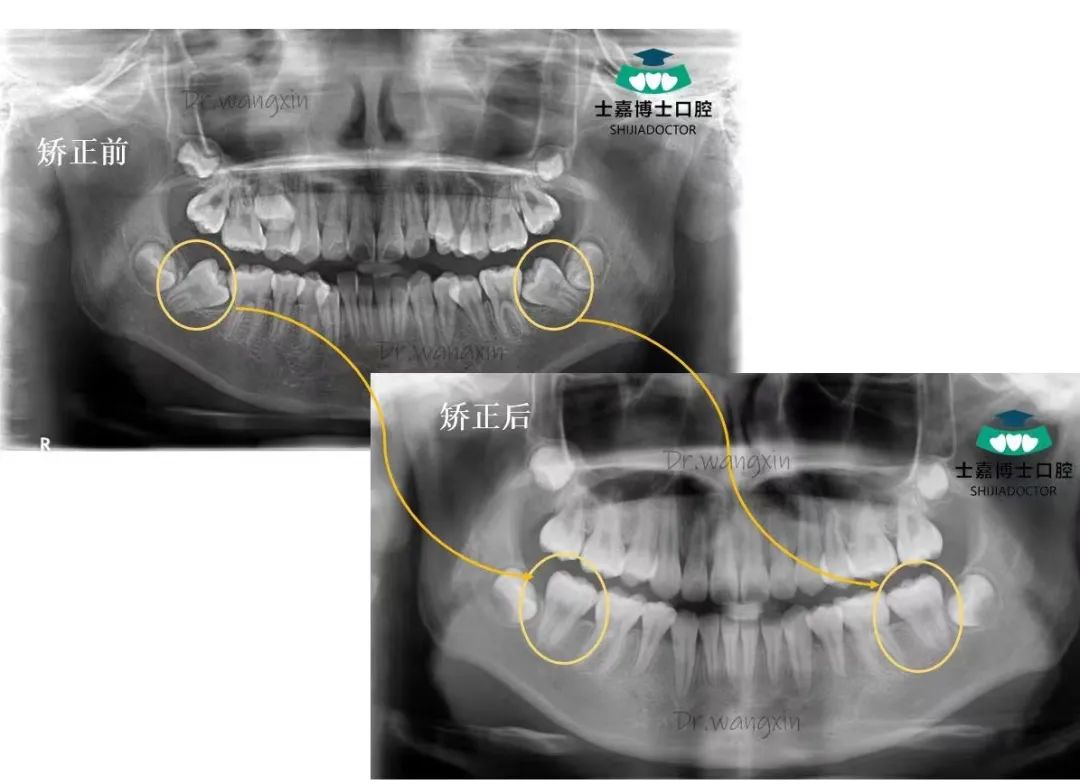

王新,口腔医学硕士,山东省首批隐适美认证医师、隐适美青年讲师;时代天使认证讲师;2008年起跟随张士杰教授从事口腔正畸工作,并成立博士口腔数字化正畸诊疗中心,负责医护团队的带教培训和管理工作。擅长:儿童错颌畸形的预防矫治及阻断矫治,青少年及成人各类错合畸形的矫治(固定矫正、隐形矫治、舌侧矫治)、严重骨性错颌畸形的正畸-正颌手术治疗、错颌畸形伴有牙周病、缺失牙等复杂病例的多学科联合治疗等。